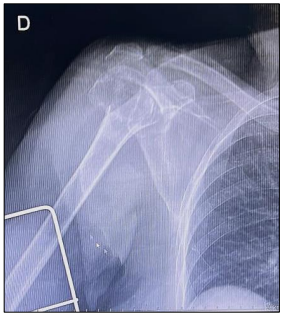

Paciente L.C.M., orientado e lúcido, afebril, diabético, hipertenso, tabagista, etilista, teve uma vertigem seguida de queda quando estava em posição ortostática acerca do solo. Foi levado ao pronto-socorro, no qual foi realizado exame de radiografia, apresentado na imagem.